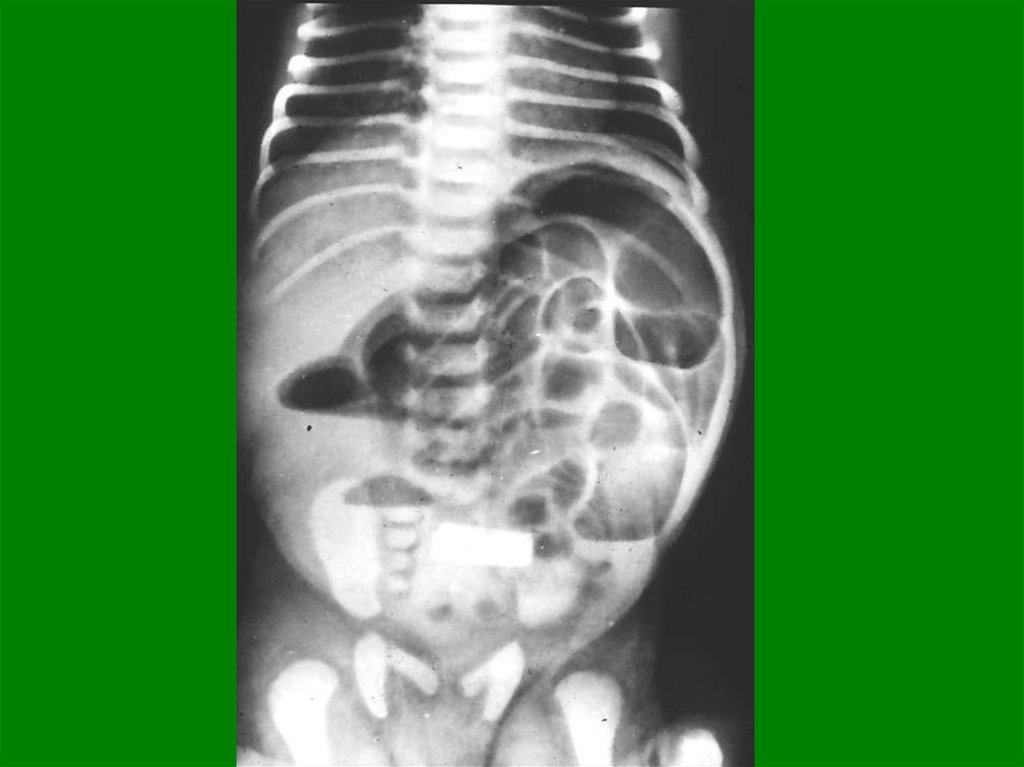

63. Множе-ствен-ные газовые уровни

Множественные

газовые

уровни